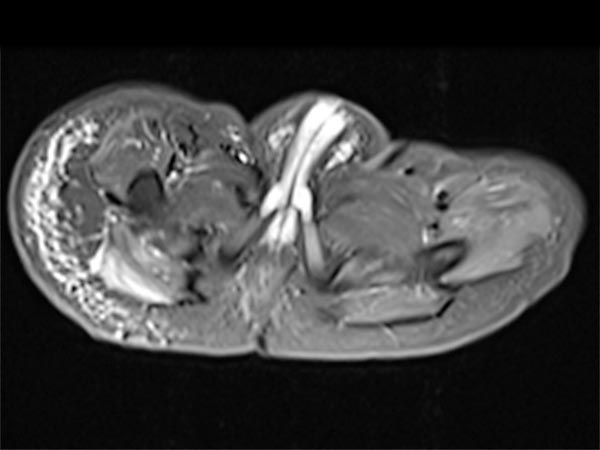

In corresponding T2-weighted, fat-saturated MRI, the tumor shows hypointense parts (hemorrhages), but also hyperintense parts and is overall very inhomogeneous and blurred. The surrounding fat tissue is saturated with lymphedema.

This surrounding subcutaneous lymphedema (hyperintense in axial T2-weighted, fat-saturated MRI ) is a typical feature of kaposiform hemangioendothelioma and also extends significantly in the surrounding area.